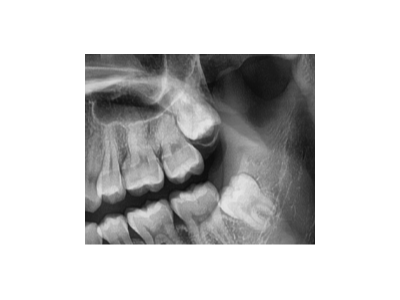

根管治療的全過(guò)程主要包括術(shù)前檢查和診斷、局部麻醉、開(kāi)髓、根管預(yù)備、根管消毒,以及根管充填、術(shù)后修復(fù)。1、術(shù)前檢查與診斷:患者先到口腔科進(jìn)行全面檢查,包括患牙的齲壞程度、牙髓活力測(cè)試、叩診等,以確定患牙…

種植牙是一種常見(jiàn)的牙齒修復(fù)方式,術(shù)前準(zhǔn)備對(duì)于手術(shù)的成功和術(shù)后恢復(fù)至關(guān)重要。以下是種植牙術(shù)前的主要準(zhǔn)備工作:一、全面口腔檢查與評(píng)估口腔檢查:包括牙齒、牙齦、咬合關(guān)系、頜骨狀況等。影像學(xué)檢查:全景片(曲面…